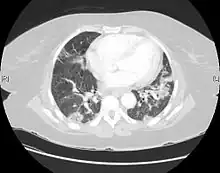

| CT scan of a patient with UIP. There is interstitial thickening, architectural distortion, honeycombing and bronchiectasis. | |

UIP may be diagnosed by a radiologist using computed tomography (CT) scan of the chest, or by a pathologist using tissue obtained by a lung biopsy.

Radiologically, the main feature required for a confident diagnosis of UIP is honeycomb change in the periphery and the lower portions (bases) of the lungs.[3]

On high-resolution computed tomography (HRCT), the following categories, depending on imaging findings, have been recommended by a collaborative effort by the American Thoracic Society, European Respiratory Society, Japanese Respiratory Society, and the Latin American Thoracic Society:[4]